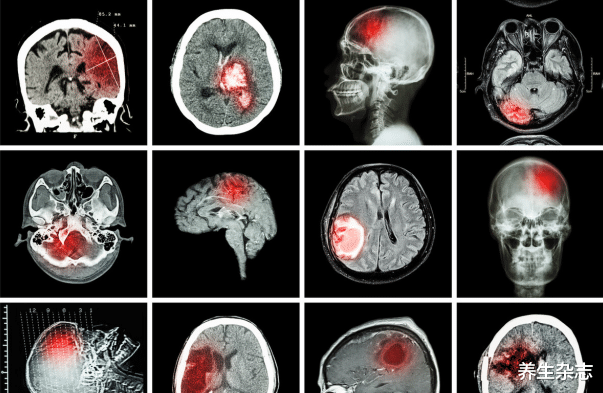

据统计 , 我国目前大概有超过3亿人患有高血脂 , 最可怕的是这个数字还在不断的上升当中 , 但是依旧有很多人不将其重视 , 知道并发症的出现 , 才后悔莫及 。

而经过医生了解 , 小杰平常就非常喜欢熬夜 , 加上饮食不合理 , 三番五次的喝酒吃烧烤 , 长此以往的生活 , 让身体代谢出现了问题 , 如果在不加以节制 , 可能还会引发脑梗、心梗等并发症 。

高血脂患者 , 身体若出现以下几种异常 , 或需要警惕一下了

- 精神不振 , 身体乏力;

- 头晕头痛;说话不清;

- 四肢经常发麻 , 走路一边倾斜;

- 眼神呆滞 , 容易眼花;

- 失眠健忘 , 胸闷心悸;